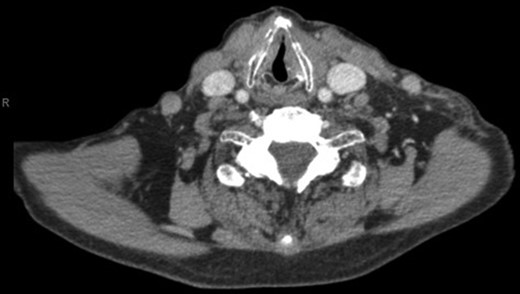

With a working differential of parapharyngeal space infection and possible malignancy, the patient was referred for a computed tomography (CT) scan of the neck and thorax with contrast. The patient was also started empirically on intravenous co-amoxiclav as treatment for neck space collection. CT imaging, performed 24 h after admission, revealed no evidence of malignancy or indeed any paraphayrngeal space collection. Few small lymph nodes were noted on the left side of the neck, but were deemed to be reactive in nature, and left vocal cord palsy was evident (Fig. 1). The key finding was that of a left sternoclavicular joint collection and closely associated superficial anterior chest wall, soft tissue swelling and oedema (Fig. 2). This inflammatory process was also noted deep to the manubrium and sternum and extending somewhat into the mediastinum with evident enlarged mediastinal lymph nodes (Fig. 3). The CT findings were in keeping with SSA with associated superficial and deep tissue inflammation and oedema. With no other cause found, the vocal cord palsy was attributed to the inflammation within the mediastinum, which in turn was caused by superficial burn from hot water bottle use.

Computed tomography. A 67-year-old male with SSA. Findings: left vocal cord palsy indicated by the para-median position of the left vocal cord in comparison with the right. Technique: contrast-enhanced axial CT of the neck and thorax.